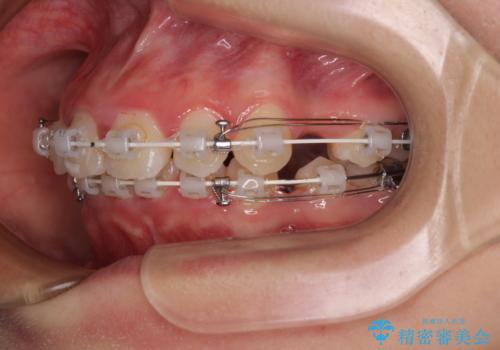

- 矯正装置

- 審美装置

- 下唇の上に乗っかってしまうくらい前歯が飛び出していることを気にして来院された患者様です。

唇を閉じようとするとオトガイ部に力が入ってしまい、うまく閉じることができない状態であったため、上下左右の第一小臼歯4本を抜歯して、ワイヤー装置にて矯正治療を行うこととしました。